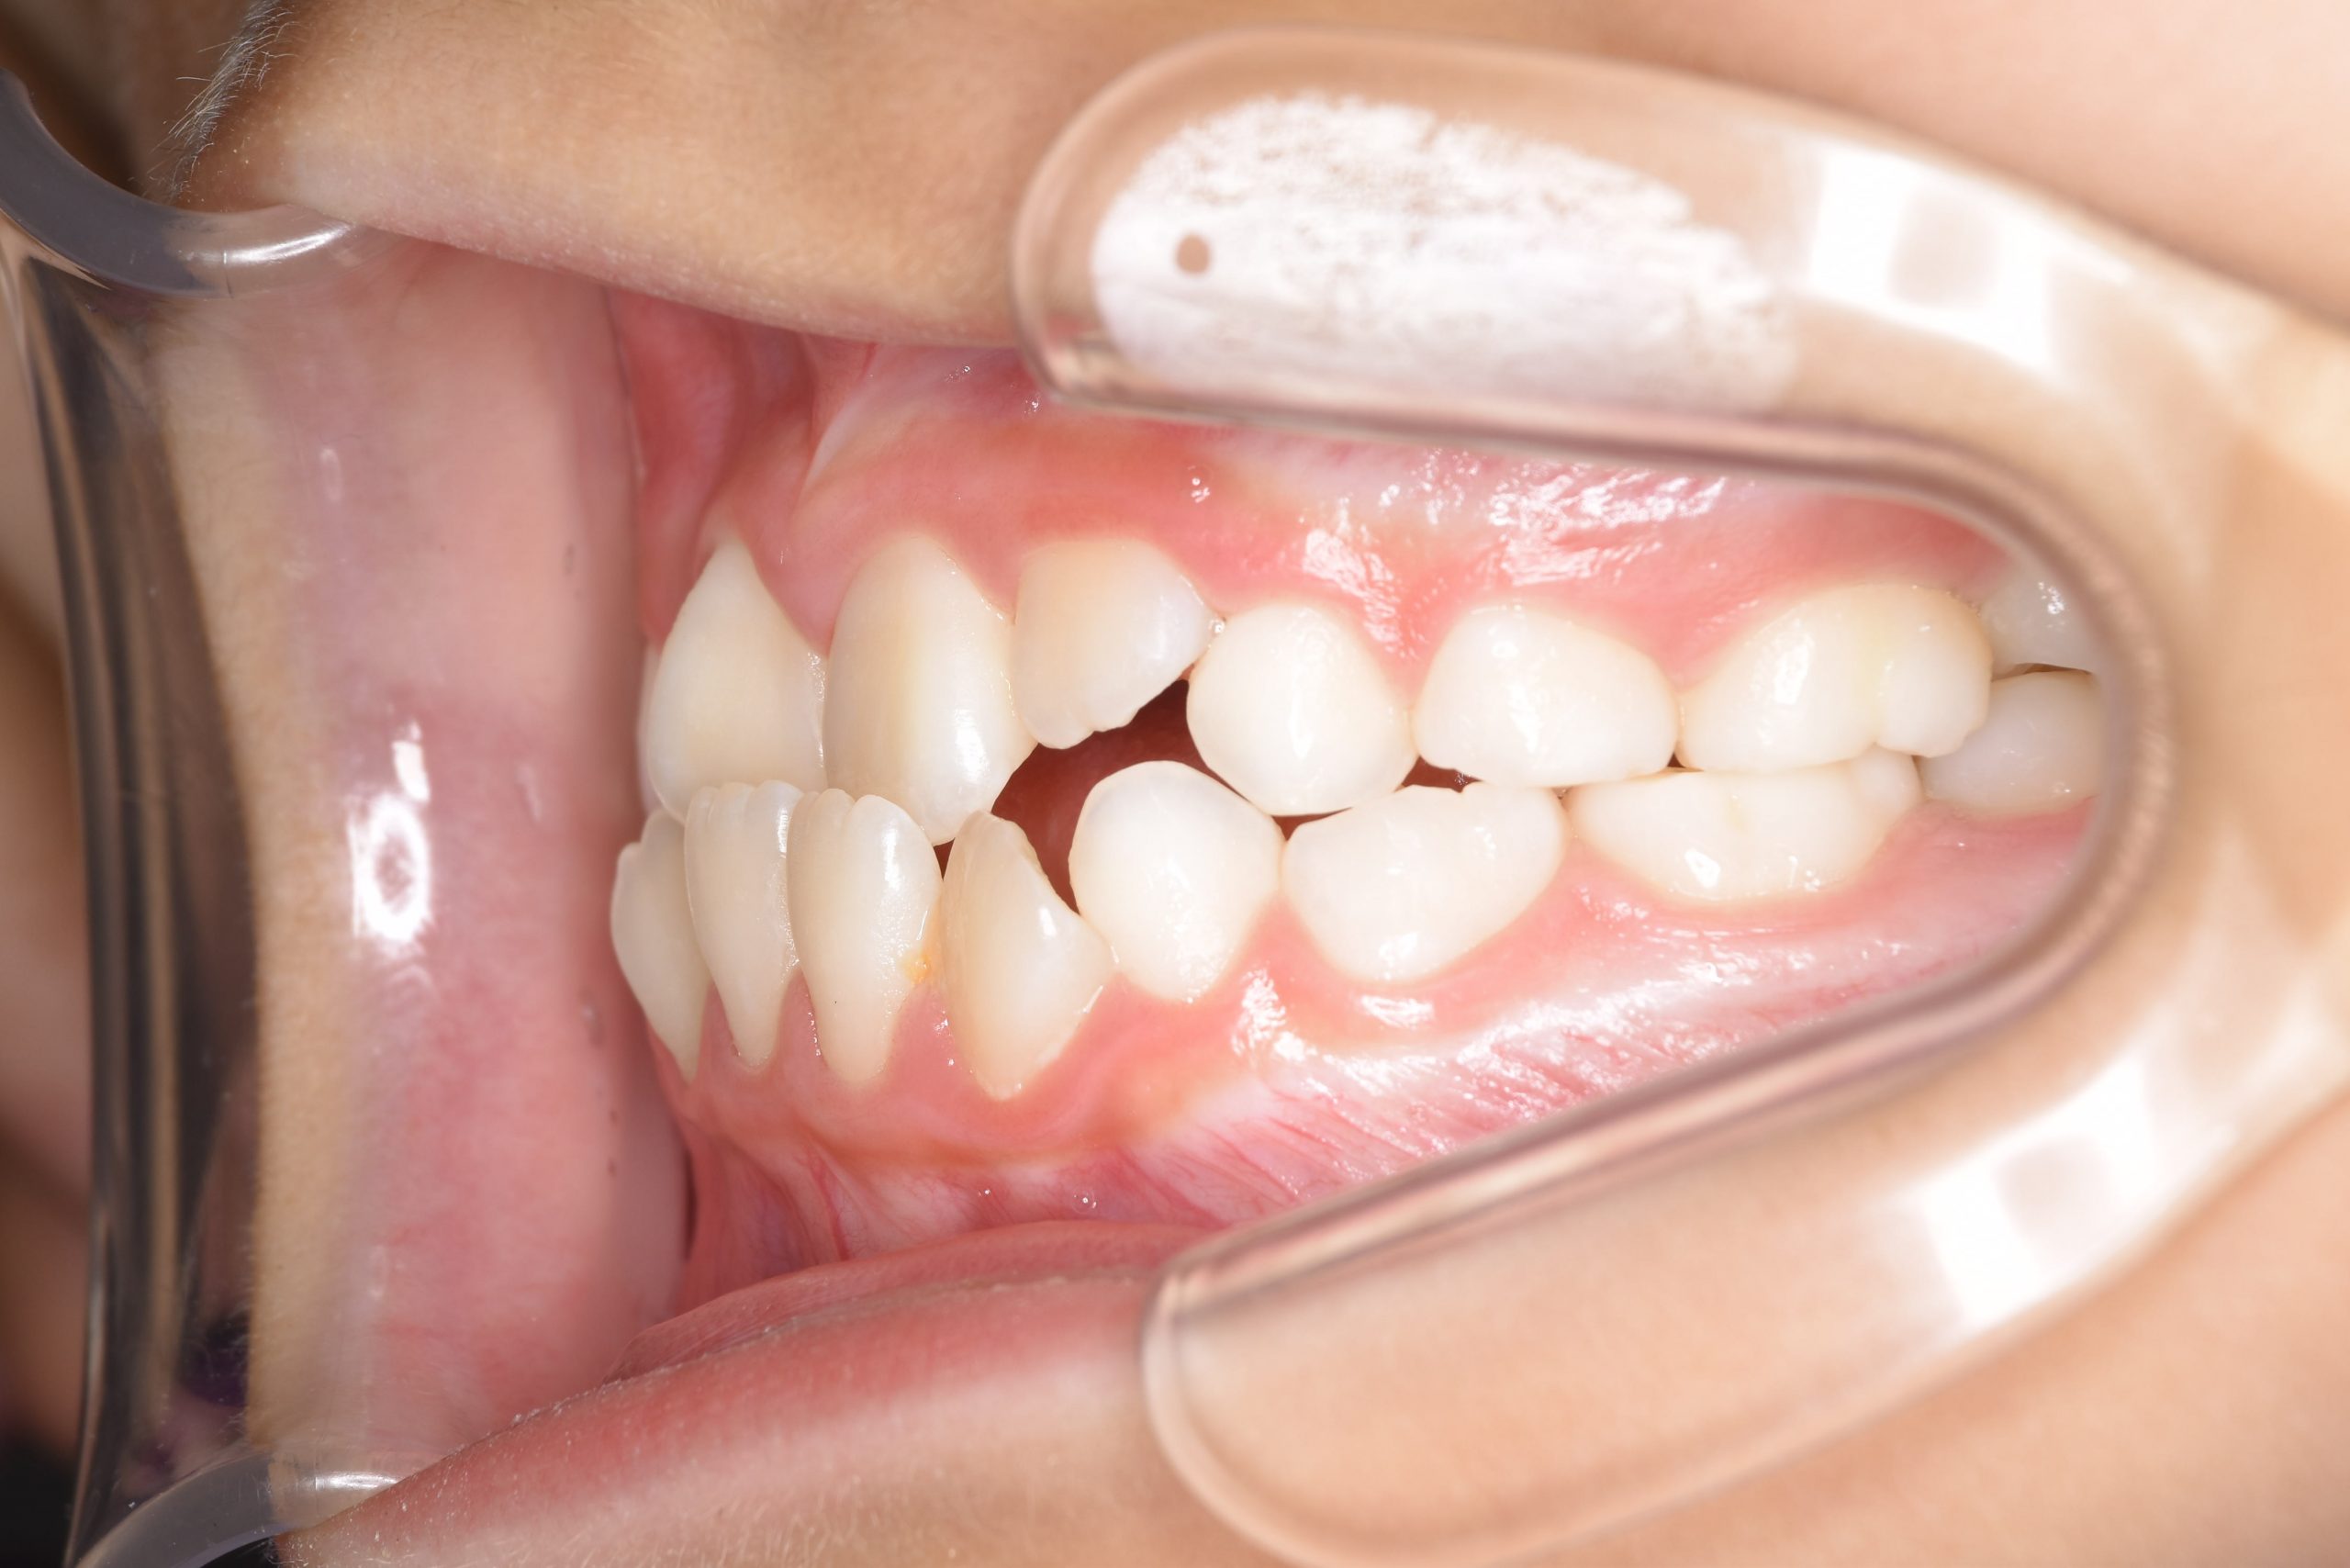

アフター

主訴 受け口

施術内容 上顎急速拡大装置と下顎リンガルアーチを用いて上下顎骨を拡大した。

上顎前方牽引装置を用いて上顎骨を前方に成長促進させた。

その後マウスピース型矯正装置で歯牙を配列し良好な咬合を獲得した。

治癒期間 2年9ヶ月間